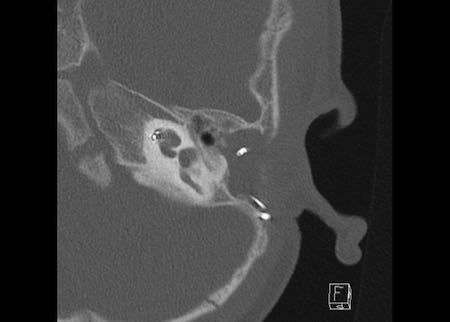

Ca lâm sàng 2

Các hình ảnh này cho thấy một điện cực cấy ghép bị lạc chỗ.

Điện cực ốc tai được đưa vào phía dưới vòng đáy của ốc tai và kết thúc ở vùng hạch gối (geniculate ganglion).